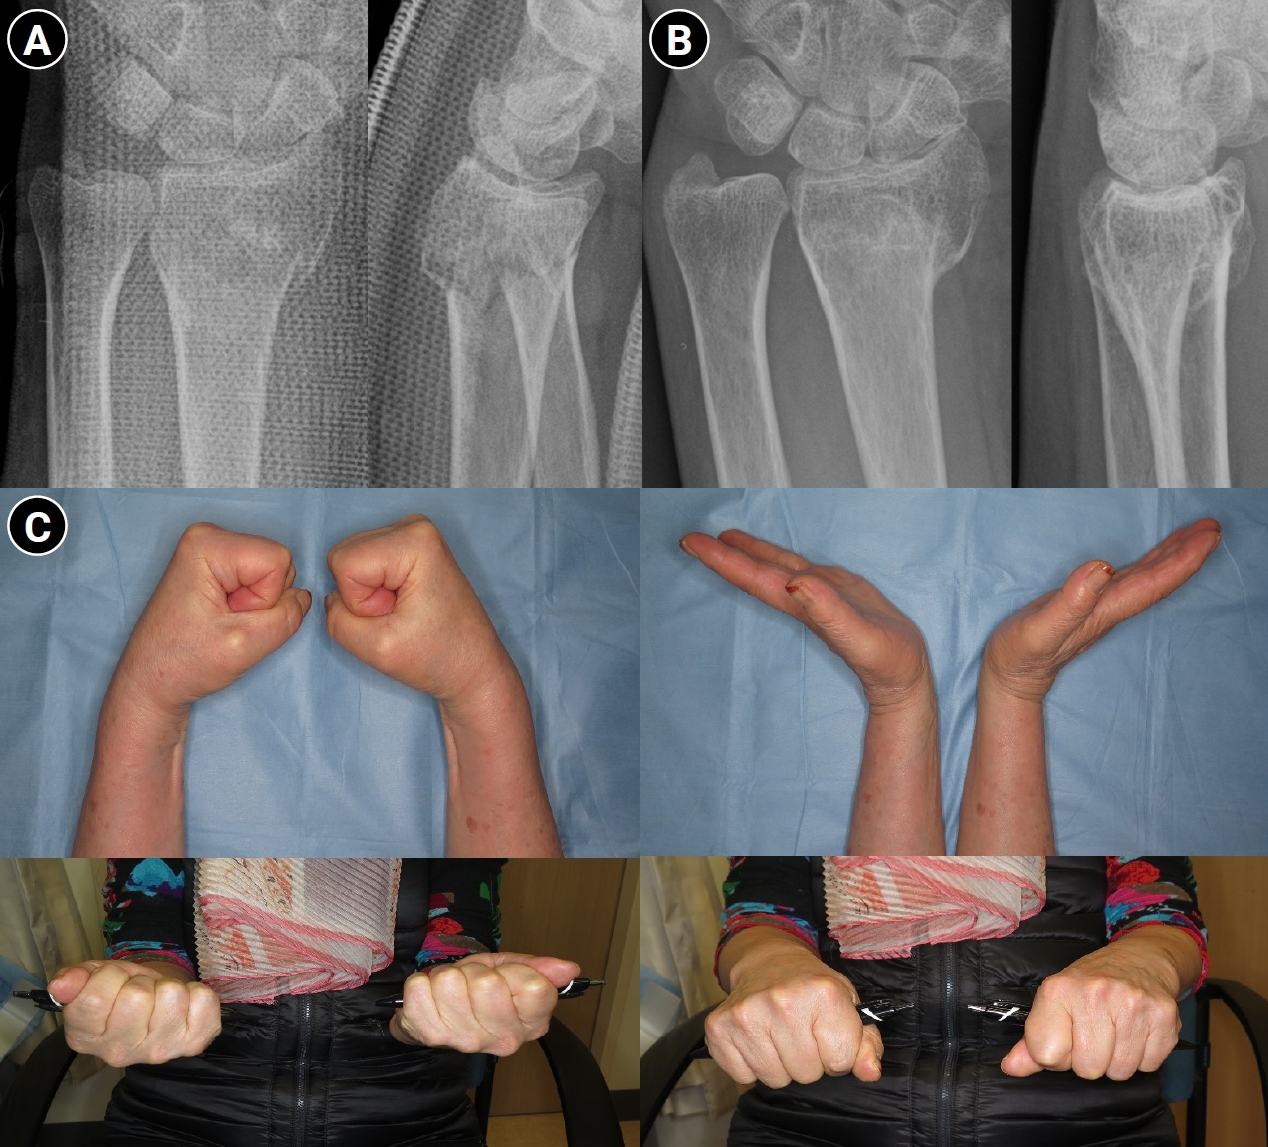

Rather than applying strict radiographic criteria uniformly across all patients, more stringent criteria may be appropriate for younger, active individuals, while more flexible thresholds may be suitable for elderly patients with comorbidities or low functional demands. In particular, several studies have reported that unsatisfactory radiographic results do not always correlate with unsatisfactory functional outcomes in elderly patients [29,30]. Kyung et al. [31] reported that dorsal metaphyseal comminution did not significantly affect radiographic or functional outcomes in patients treated nonoperatively. Kim et al. [32] compared elderly patients (≥65 years) treated nonoperatively versus operatively for unstable distal radius fractures and found that although radial shortening was more pronounced in the nonoperative group, functional evaluation and wrist range of motion did not differ significantly between groups. A recent randomized trial of intraarticular fractures found that intraarticular incongruity did not significantly affect functional outcomes, even though radiographic differences were present (Fig. 2) [16]. These findings support the premise that in elderly patients with lower functional demands, nonoperative treatment can achieve satisfactory outcomes even when anatomical restoration is not perfect.

Fig. 2.

Outcome of conservative treatment in an older patient with a displaced distal radius fracture. Radiographs of a 71-year-old female patient. (A) Wrist anteroposterior and lateral radiographs obtained after initial reduction, demonstrating distal radius and ulnar styloid fractures with intraarticular comminution of the left wrist. Volar tilt and radial length were well restored after reduction. (B) Wrist radiograph obtained 1 year after trauma, showing radial shortening and dorsal tilt of the distal radius. (C) Range of motion of the left wrist was slightly decreased compared with the right side; however, the patient was able to perform daily activities without pain at one year after trauma.

Fig. 2. Outcome of conservative treatment in an older patient with a displaced distal radius fracture. Radiographs of a 71-year-old female patient. (A) Wrist anteroposterior and lateral radiographs obtained after initial reduction, demonstrating distal radius and ulnar styloid fractures with intraarticular comminution of the left wrist. Volar tilt and radial length were well restored after reduction. (B) Wrist radiograph obtained 1 year after trauma, showing radial shortening and dorsal tilt of the distal radius. (C) Range of motion of the left wrist was slightly decreased compared with the right side; however, the patient was able to perform daily activities without pain at one year after trauma.